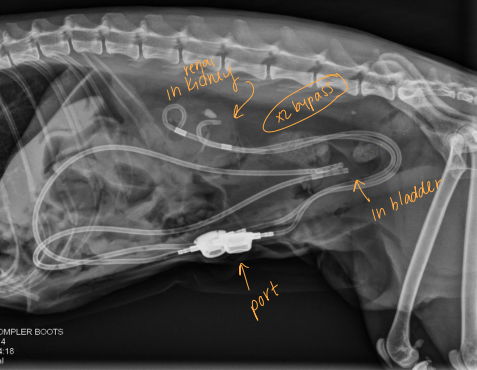

Ureteral Surgical Procedures

Subcutaneous ureteral bypass (SUB): Obstruction, cats

Replaces ureterotomy, pyelolithotomy

Place catheter from renal pelvis to bladder apex

Ureteral stent: for dogs w/ obstruction

Tx: SUB (C), Ureteral stent (D)